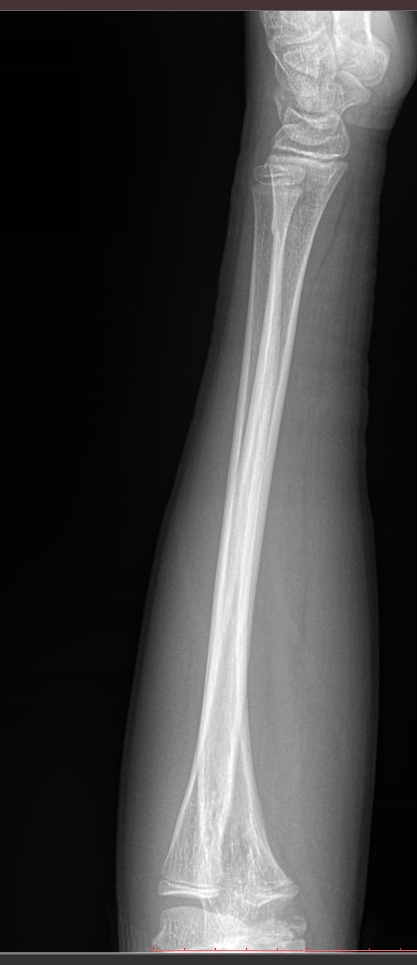

В предплечье входят 2 кости ― лучевая и локтевая. Вместе они соединяют кисть с плечом и обеспечивают движение и повороты руки. Переломы костей происходят в наиболее тонких местах ― ближе к суставам. Реже встречаются костные и мышечные патологии и онкология.

Обследование поврежденного или пораженного предплечья начинают с рентгенографии. Современное оборудование несет минимальное количество обучения и позволяет делать несколько снимков подряд, например, для контроля хирургического лечения. В снимок кроме собственно локтевой и лучевой кости попадают оба смежных сустава ― локтевой и лучезапястный. Также видны и мягкие ткани.

Что покажет рентген предплечья

• Костно-травматические изменения лучевой и локтевой костей;

• Патологические изменения в костной ткани;

• Состояние мягких тканей;

• Состояние прилежащих суставов, их заболевания и травмы;

• Новообразования и метастазы данной области.